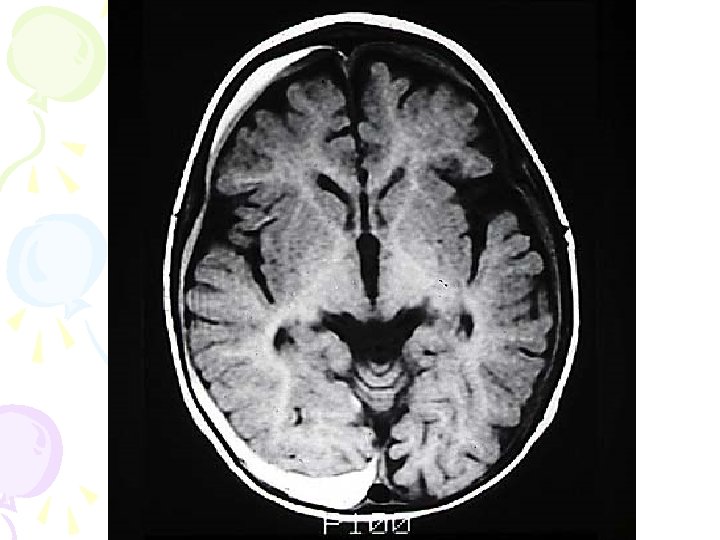

Magnetic Resonance Imaging (MRI) • A technique that uses magnetic fields and radio waves to produce computer-generated images that allow us to see structures within the brain